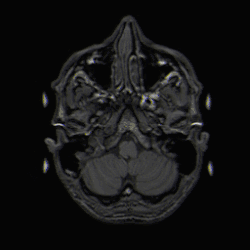

-

Einzelbild einer Magnetresonanz- tomographie eines menschlichen Gehirns; animierte Version mehrerer transversaler Schnittebenen -